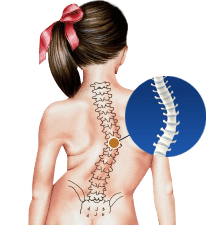

Congenital Scoliosis

Congenital scoliosis is the lateral curvature of spine that occurs in children